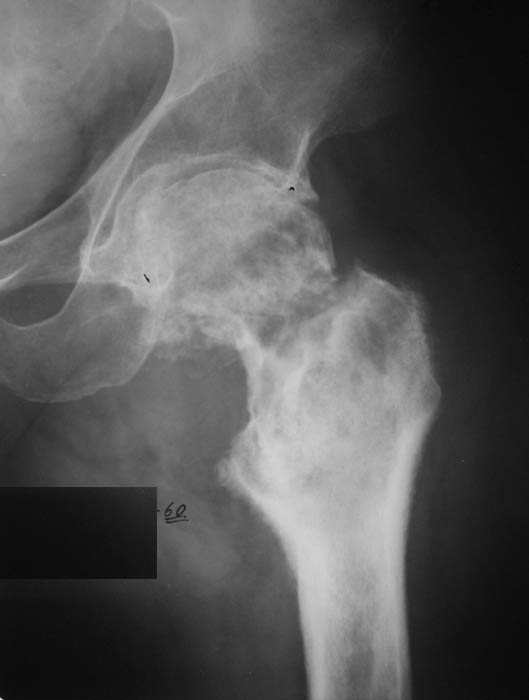

И снова вопрос по эндопротезированию: Пациенту 51 год. Болен с 2000 г, когда отметил умеренные, нараостающие боли в в/3 левого бедра, прогрессирующую контрактуру лев Т/Б сустава.

05.12.04 после падения на бедро боли резко усилились, нога стала неопорной. На рентгенограмме обнаружен патологический перелом шейки бедренной кости. Обследован в отделении костной онкологии. Результат биопсии: асептический некроз проксимального отдела бедренной кости. Вопрос: выбор технологии эндопротезирования - цементная или бесцементная версия. Заранее благодарю! С уважением,А.В.Владзимирский

Проксимальный отдел бедра не виден достаточно на представленных рентгенограммах; но то, что видно, как раз наводит на мысли о цементной фиксации - цилиндрический канал, измененный calcar, кистозные изменения в области большого вертела и т.д.

Как то очень подозрительно выглядит проксимальный отдел бедра для такого очень простого гистологического заключения. Вы уверены, что гистология настолько благополучна и в каком варианте она выполнялась: пункционная или открытая с забором костного блока? Не уверен на все сто , но область проксимального отдела бедра - одно из излюбленных мест для гигантоклеточной опухоли, которая зачастую озлакочествляется (имел два подобных наблюдения). Из своей практики могу сказать, что, к сожалению, информативность пункционной биопсии не сравнима с открытой техникой. Поэтому прежде чем решать цементный или бесцементный протез использовать, я бы повторил биопсию в сочетании со сканированием скелета, сывороточная щелочная фосфатаза, кальций, фосфор сыворотки, СОЭ, С- реактивный белок,

Soglasen s Евгений И Чекашкин, proximal Femur does not look right. Sarcoma? Pagets, Osteomyelitis?. Technicality of the implantaion will be dependent upon underlying pathology, and the surgeon's level of comfort.

Действительно, проксимальный отдел бедра выглядит подозрительно. По-моему напоминает болезнь Педжета. Кстати, гистологическое заключение в таком случае часто звучит как "хроническое воспаление", "асептический некроз с элементами лейкоцитарной инфильтрации" и т.п. Далеко не все патоморфологи имеют достаточный опыт для дифференцировки костной патологии.